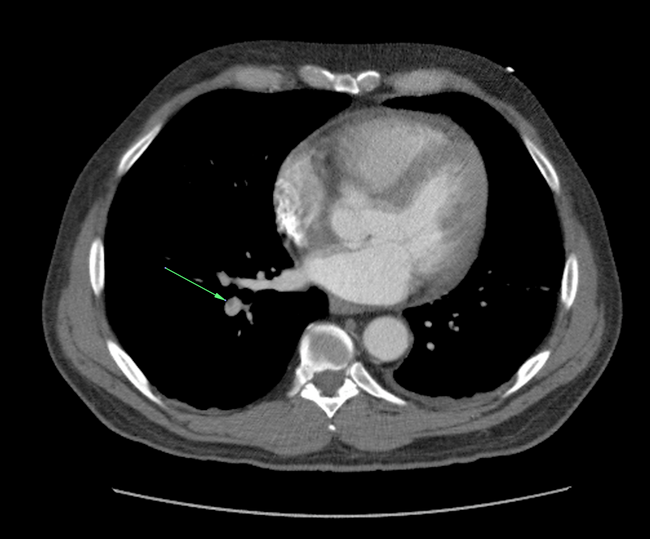

Bilateral Pulmonary Emboli

Ascending Aortic Aneurysm